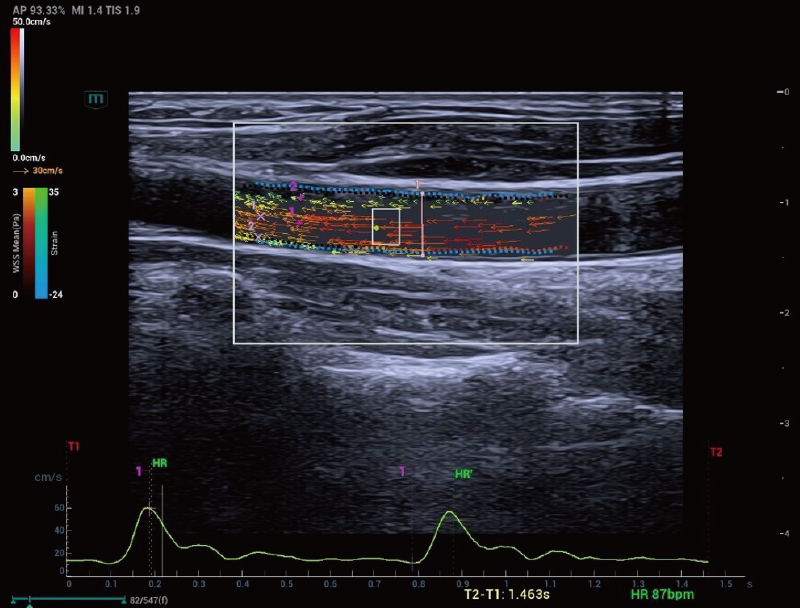

Resona A20 introduce una nuova generazione di strumenti per l'analisi quantitativa vascolare, con l'analisi della velocit├Ā dell'onda di polso vascolare e dello stress di parete basata sui dati RF. Questi progressi aiutano a valutare la sclerosi vascolare arteriosa.

Analisi dello stress di parete e V Flow

Arteria carotide | V Flow